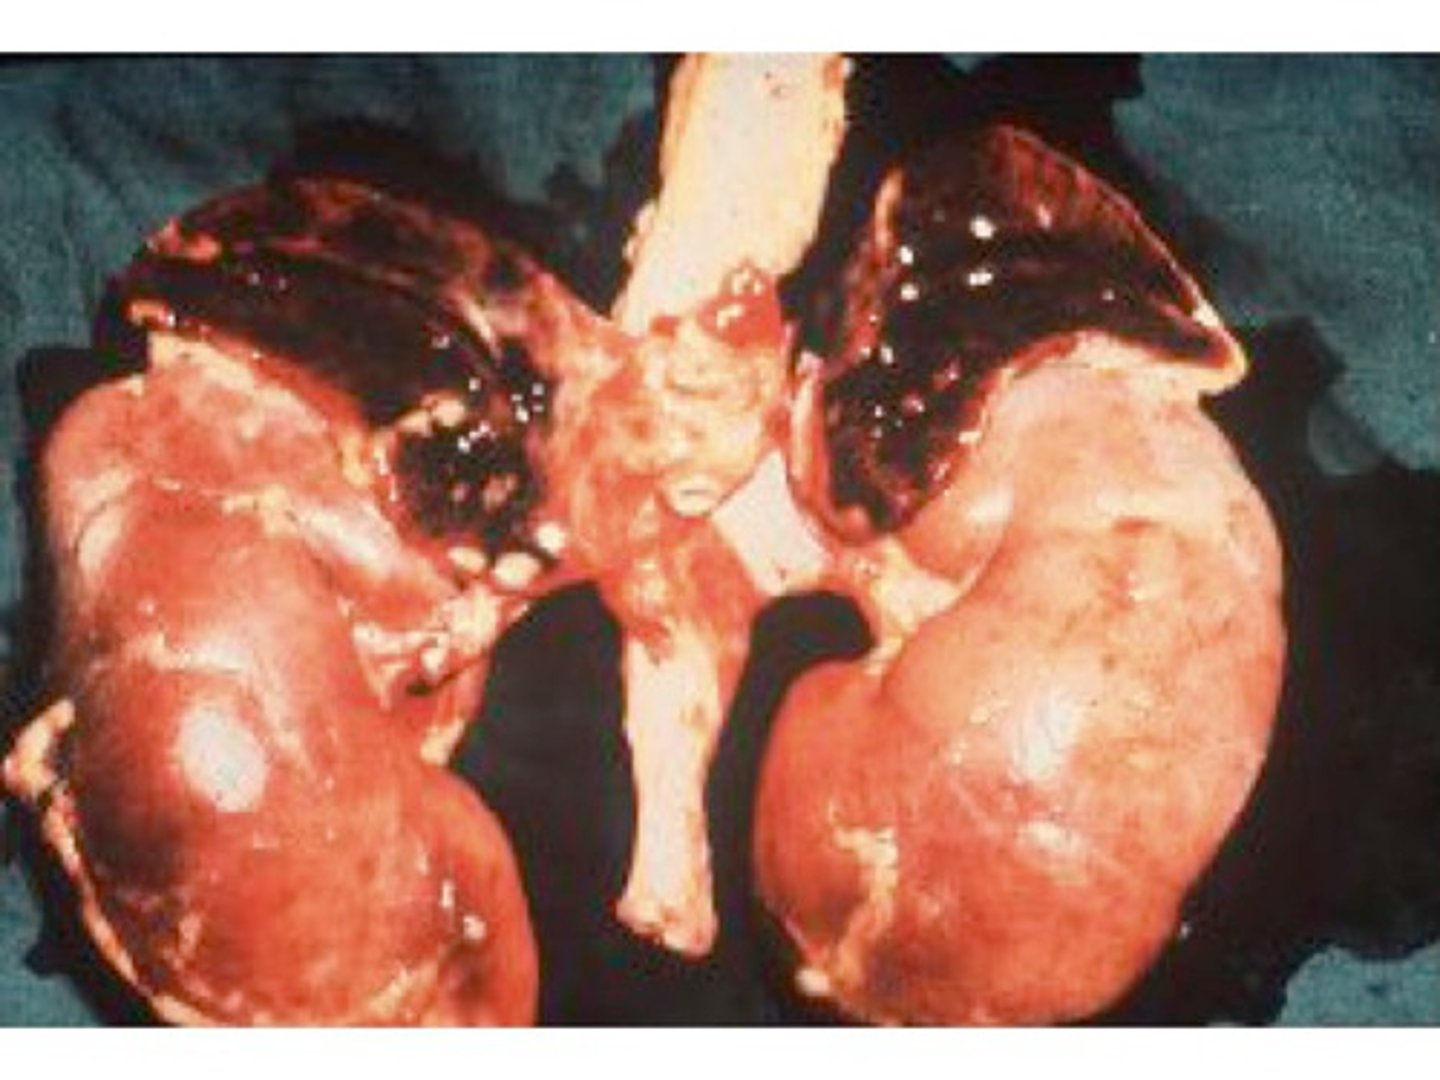

Abdominal pain, ascites, hepatomegaly

Budd-Chiari Syndrome (posthepatic venous thrombosis, can be related to Polycythemia vera)